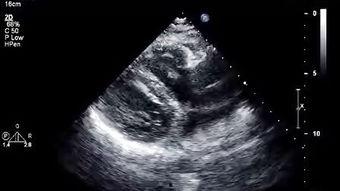

心脏彩超,顾名思义,就是利用超声波技术来观察心脏的结构和功能。它能够清晰地显示心脏的各个部位,包括心房、心室、瓣膜等,还能观察到心脏的跳动和血流情况。对于心脏疾病的诊断和治疗来说,心脏彩超就像是一把“秘密武器”,能够帮助医生们更好地了解患者的病情。